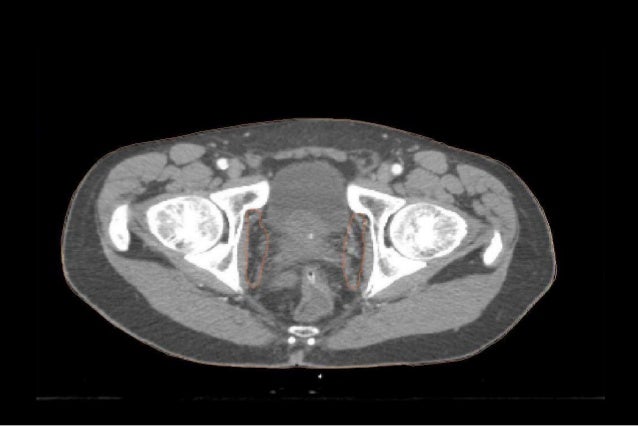

Brachytherapy wikipedia. Brachytherapy beads used to deal with prostate most cancers. Arrow marks beads. Synonyms inner radiotherapy, sealed source radiotherapy, curietherapy, endocurietherapy. External beam radiation for prostate most cancers assessment. External beam radiation for prostate most cancers comprehensive evaluation covers dangers, consequences of prostate cancer radiation therapy. Localized prostate cancer what every guy need to recognize. Radiotherapy for prostate most cancers search now! Over 85 million visitors. Solution questions, solve troubles, discover inspiration. Prostate cancer memorial sloan kettering cancer middle. Prostate most cancers has a tendency to increase in older guys and often has no significant signs. Examine more about this disorder, the second one maximum typically recognized cancer in men. Prostate most cancers word list webmd. Webmd offers a comprehensive glossary of phrases you may pay attention all through prostate cancer checking out, analysis, remedy, and recuperation.

Prostate cancer bc most cancers organisation. Symptoms and symptoms. Inside the early degrees, there may be no symptoms. Now and again prostate most cancers is discovered coincidentally after surgical treatment for benign (noncancerous) prostate. Comparative effectiveness of radical prostatectomy and. Goal to evaluate the survival effects of patients handled with surgical operation or radiotherapy for prostate cancer. Design observational. Prostate cancer prostate cancer cme mastering middle. Evaluation prostate most cancers symptoms and symptoms of prostate most cancers. Recognize prostate cancer remedy, together with prostate cancer surgical treatment, and learn about prostate cancer. Radiotherapy for prostate most cancers seek now! Over eighty five million site visitors. Prostate most cancers remedy; stage i to iii cancer uptodate. Prostate most cancers is a cancer of the prostate gland. The prostate is an organ that forms a hoop across the urethra, close to its connection to the bladder (). The urethra. Prostate cancer facts cancer studies united kingdom. Authoritative updates for clinicians on prostate most cancers remedy, psa screening, prostatectomy vs surveillance, chemoprevention, and radiation and proton therapy. Prostate most cancers dr. Robert zaid. Goal to examine the survival results of patients treated with surgical treatment or radiotherapy for prostate most cancers. Layout observational take a look at. Putting sweden, 19962010.